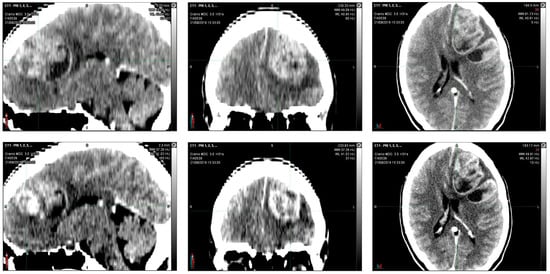

In August 2016, in the emergency department, a 36-year-old woman, after 15 days of headache and unresponsiveness to non-steroidal anti-inflammatory drugs (NSAID), underwent a computed tomography scan (CT scan). The CT scan of the brain, performed with contrast medium, showed, in the left fronto-parietal area, two voluminous formations and inhomogeneous contiguous focalities of 52 × 41 mm and 40 × 20 mm, respectively, characterized by irregular peripheral impregnation and contextual necrotic–colliquative areas, with surrounding perilesional digitiform hypodensity, compression of the lateral ventricle, and contralateral shift of the midline structures (1 cm) (Figure 1).

Computerized tomography (CT) scan with contrast medium performed at initial diagnosis (21 August 2016) showed, in the left fronto-parietal area, two voluminous formations and inhomogeneous contiguous focalities of 52 × 41 mm and 40 × 20 mm, respectively, characterized by irregular peripheral impregnation and contextual necrotic-colliquative areas, with surrounding perilesional digitiform hypodensity, compression of the lateral ventricle, and contralateral shift of the midline structures (1 cm).